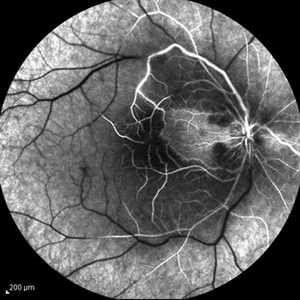

Behcet's Disease Behcet's DiseaseMar 13 2013 by Hamid Ahmadieh, MD Mid phase FA of the right eye of a 23-year-old man with retinal vasculitis and branch retinal vein occlusion (BRVO) due to Behcet's disease . Photographer: Solmaz Shahmohammad, Negah Eye Center, Tehran Imaging device: Heidelberg Spectralis Condition/keywords: branch retinal vein occlusion (BRVO), retinal vasculitis